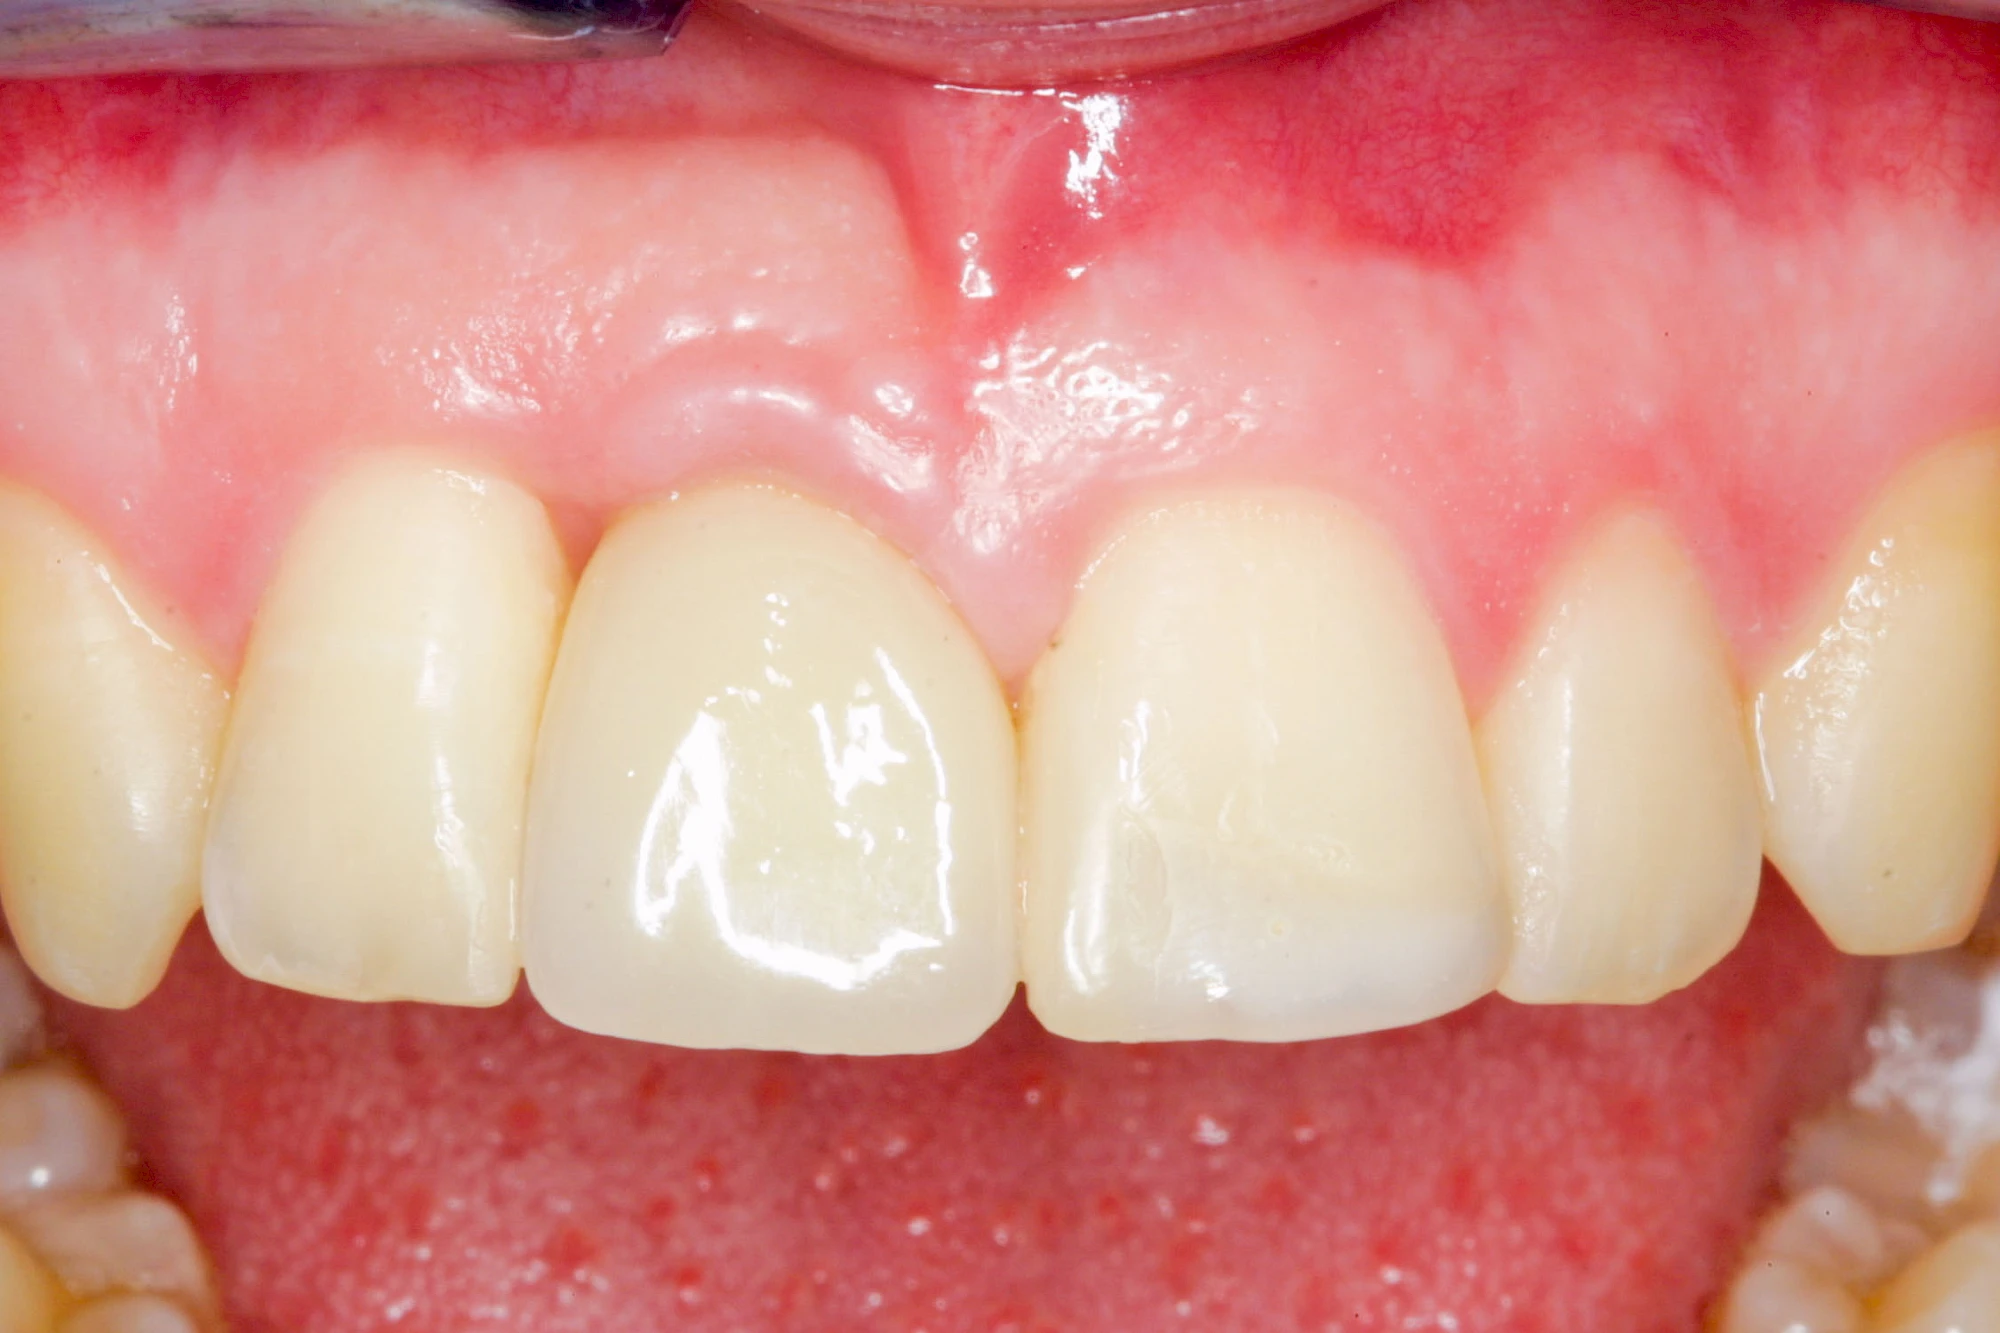

Implantate sind künstliche Zahnwurzeln. Nach einer gewissen Einheilzeit im Knochen (meist 3-6 Monate) erfolgt über einen separaten Aufbau (Abutment) die Befestigung einer Krone bzw. Brücke oder Zahnprothese.

Fehlen einzelne Zähne und die Nachbarzähne sind unbeschadet oder gut zahnärztlich versorgt, werden immer häufiger Implantate gewählt, um die Lücken zu schließen. Auch bei größeren oder verteilten Lücken, wenn keine herausnehmbare Prothese gewünscht ist, werden Implantate für Kronen- bzw. Brückenversorgungen gesetzt. In Einzelfällen entscheiden sich sogar zahnlose Patienten für eine festsitzende Versorgung auf Implantaten.